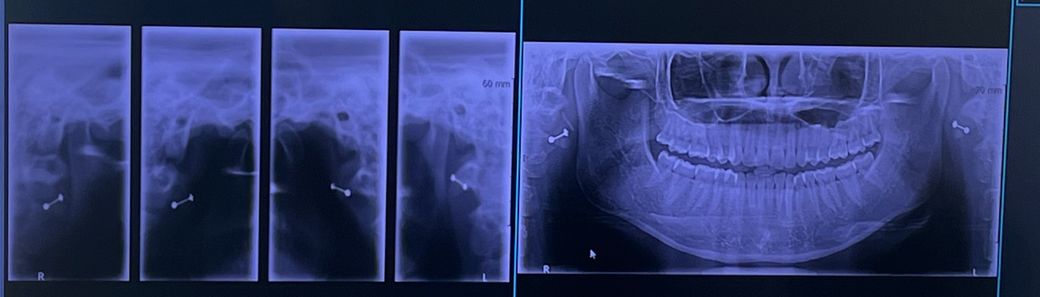

턱관절 엑스레이 한번만 봐주세요 ㅠㅠ

1. 디스크가 빠진건가요? (왼쪽 오른쪽 각각 알려주세요)

2. 뼈가 갈리고 있는 중일까요.. 소리가 나서요

3. 왼쪽과 오른쪽 마모는 어떤가요..?

4. 입을 다물고 힘을 아주조금이라도 주면 드드득 으드득 이런 소리가 나는 원인이 뭘까요? (그리고 이럴 경우 제 턱관절은 어느정도 상태인지 궁금합니다..)

5. 엑스레이 사진보고 양쪽 턱관절이 어떤지 궁금해요..

1. 하악과두 위치는 양호합니다

2. 뼈와 뼈가 직접 만나지는 않습니다. 소리는 하악과두가 디스크(관절)를 지나가면서 내는 소리입니다

3. 마모는 심하지 않습니다

4. 지속적으로 소리가 나고 불편 증상이 있다면 근이완제 약물치료보다 더 적극적인 개입이 필요합니다. 물리치료, 장치치료 등이 필요합니다.